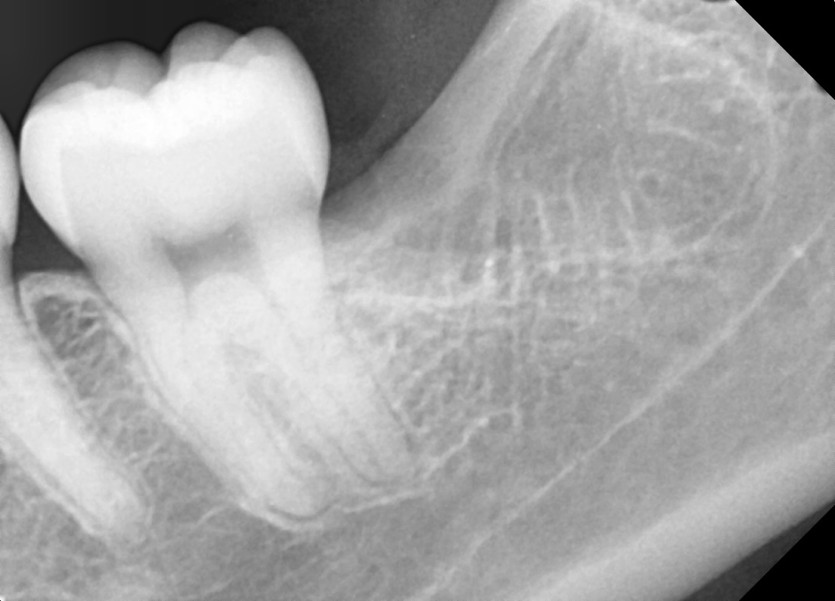

#38,48 사랑니 발치

구강 외과 전문의가 당일 발치했습니다.